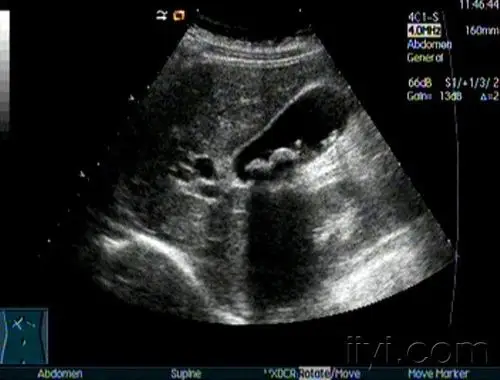

胆总管结石伴胆系扩张

图1:术前肝胆彩超图2:术前上腹ct:提示胆囊充满型结石术前检查完毕后